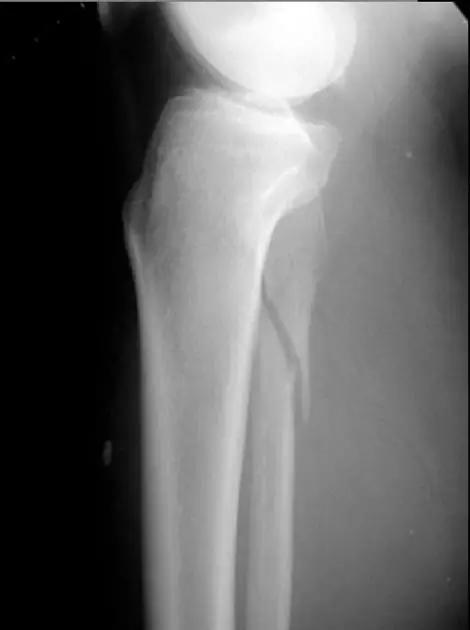

11. Bumper 骨折 (保险杆骨折)

是汽车保险杠撞击膝关节外侧,导致的胫骨平台粉碎性骨折,伴有软骨面挫裂和腓骨头骨折。初诊,X 线上正侧位很容易忽略平台的粉碎性,CT 平扫及重建可明确伤情,MRI 可了解副韧带及叉韧带情况。